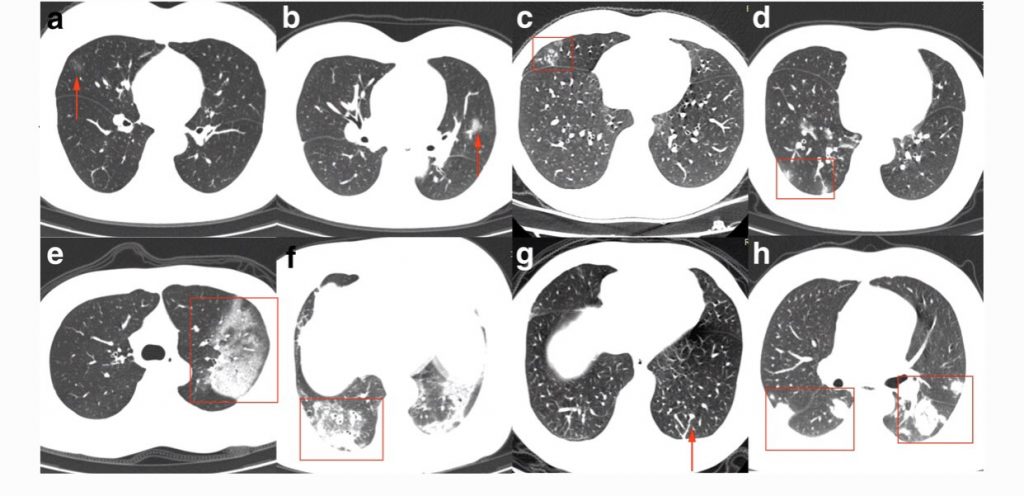

Ernstigere ziekte bij #COVID19 ontstaat als niet alleen bronchitis ontstaat, maar ook een (virale) longontsteking.

Pas bij longontsteking zie je afwijkingen op de longfoto of -scan.

In de longen vindt gaswisseling plaats en indien verstoord, kan er benauwdheid optreden.

We krijgen een steeds duidelijker beeld van de verschillende afwijkingen op de foto.

Voor de liefhebber: https://t.co/kFPzWdYzKU pic.twitter.com/bBrav2vUJo— Sander de Hosson (@shossontwits) March 1, 2020